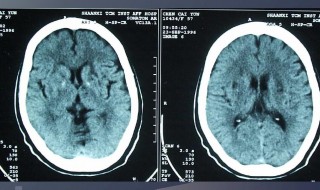

3、而多数腔隙性脑梗塞由于一般发病部位多,病灶面积小,所以又称为多发腔隙性脑梗塞。腔隙性脑梗塞的临床诊断一般是指直径在15—20毫米以下的新鲜或陈旧性脑深部小梗塞的总称。这些小动脉闭塞后,可引起多个大小不同的脑软化灶,最后形成大大小小的腔隙,它可通过头部CT确诊。常见3—10毫米的低密度区,小于2毫米的病灶CT不能显示。